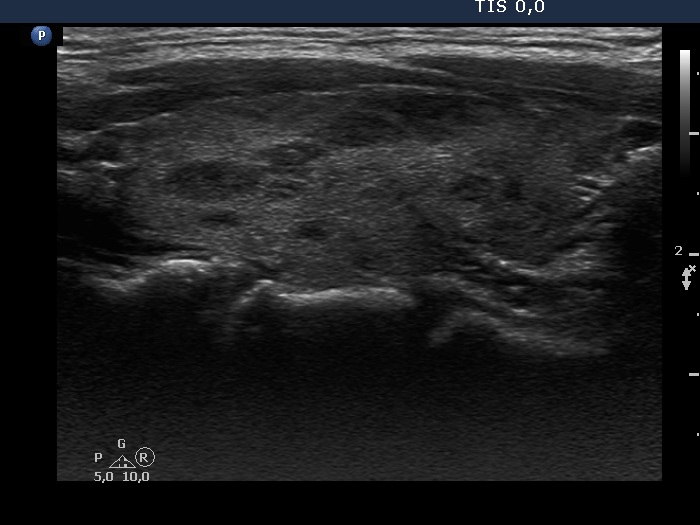

Discrete lesion or nodule in Hashimoto's thyroiditis - case 10 (95)

Follow-up investigation 38 months after the first visit (ultrasonographic picture 2)

Right lobe, longitudinal scan. Most of the hypoechogenic areas have sharp borders.